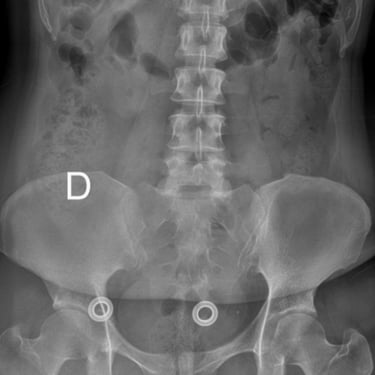

Manejo quirúrgico de la hernia lumbar con inestabilidad: enfoque moderno con FTP y TLIF

La hernia lumbar con inestabilidad vertebral es una patología frecuente que causa dolor lumbar persistente, ciática y limitación funcional, afectando la calidad de vida del paciente. Cuando el tratamiento conservador no logra resultados adecuados, la cirugía se convierte en la mejor opción terapéutica. La fijación transpedicular con tornillos (FTP) junto con la técnica TLIF (Transforaminal Lumbar Interbody Fusion) permite estabilizar la columna, descomprimir las estructuras nerviosas y lograr una adecuada fusión ósea. Este abordaje, especialmente mediante técnicas mínimamente invasivas (MISS), ofrece múltiples beneficios, como menor daño muscular, menor dolor postoperatorio y recuperación más rápida, facilitando el retorno temprano a las actividades cotidianas con mejores resultados clínicos.